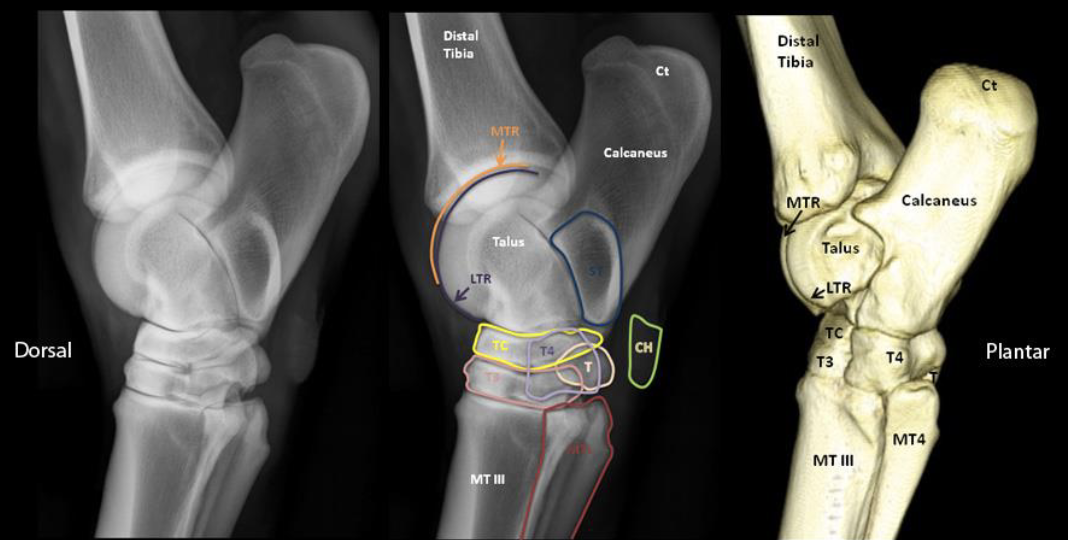

identify middle image

orange- medial trochlear ridge (of talus bone)

purple- lateral trochlear ridge (of talus bone)

blue= sustentaculum tali

green= chestnut

yellow= central tarsal bone

pink= 3rd tarsal bone

light purple= 4th tarsal bone

cream= fused 1 & 2 tarsal bone

red= metatarsal 2 and 4